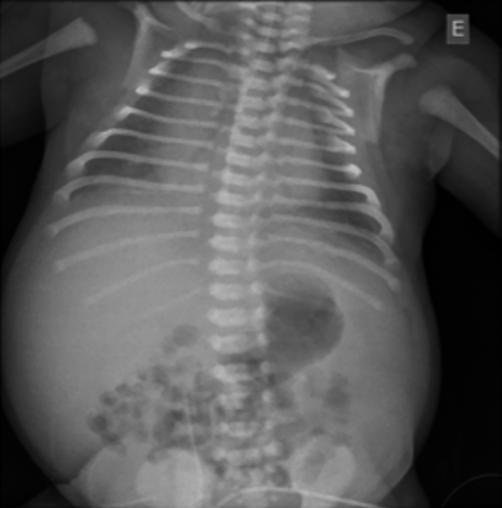

Figura 9.2.2 – Imagem radiológica de ascite.